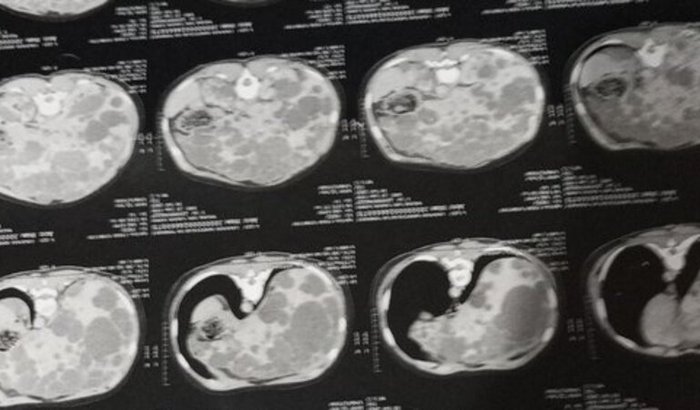

Queridos amigos, hoje venho compartilhar com vocês uma situação delicada. Minha prima está enfrentando um grave problema no fígado e precisará de transplante. Nesse processo, além da luta pela saúde, ela e a família têm enfrentado muitas despesas: remédios que nem sempre estão disponíveis pelo SUS, consultas, transporte (Uber), combustível e outras necessidades do dia a dia.